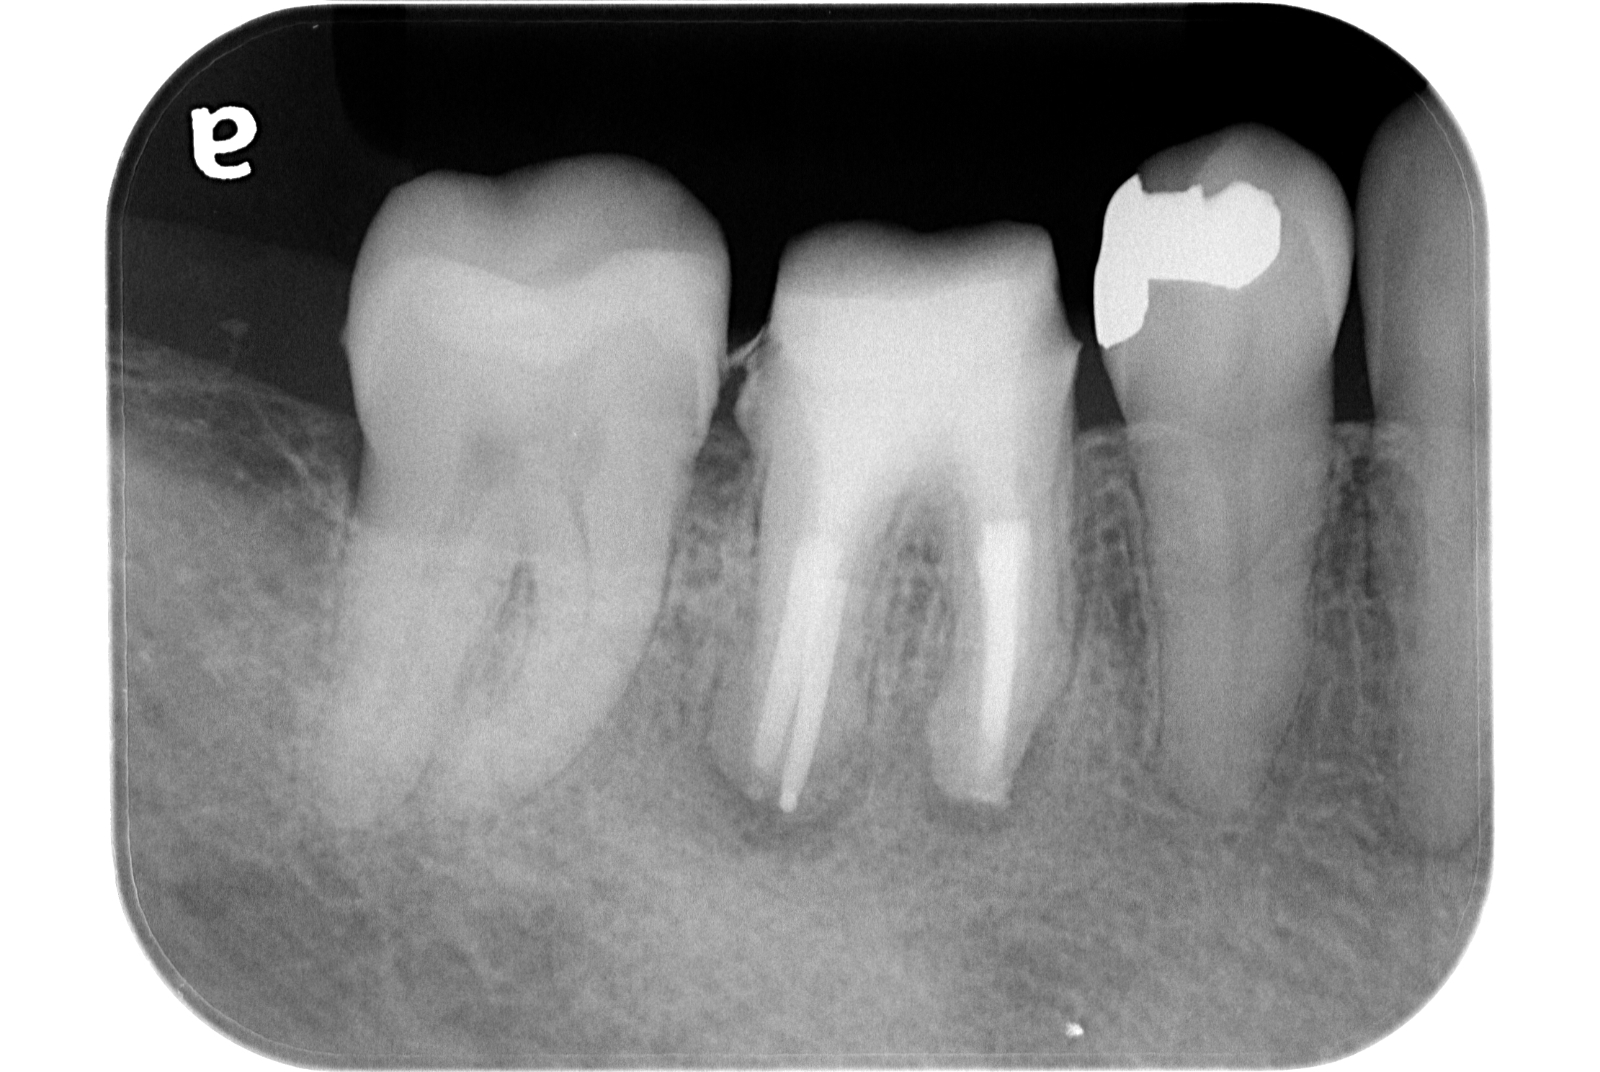

治療例 写真とレントゲン

治療前

治療後

※治療例に記載の情報はあくまでも症例に対してのものとなります。

| 費用 | 部分断断髄 44,000円(税込) |

|---|---|

| MTA 5,500円(税込) | |

| 治療期間 | 1日 |

| 治療回数 | 1回 |

| 主な副作用とリスク | 歯髄保存療法が奏功しなかった場合、根管治療へ移行します。 根管治療が必要となった場合、修復物を除去することがあります。 |